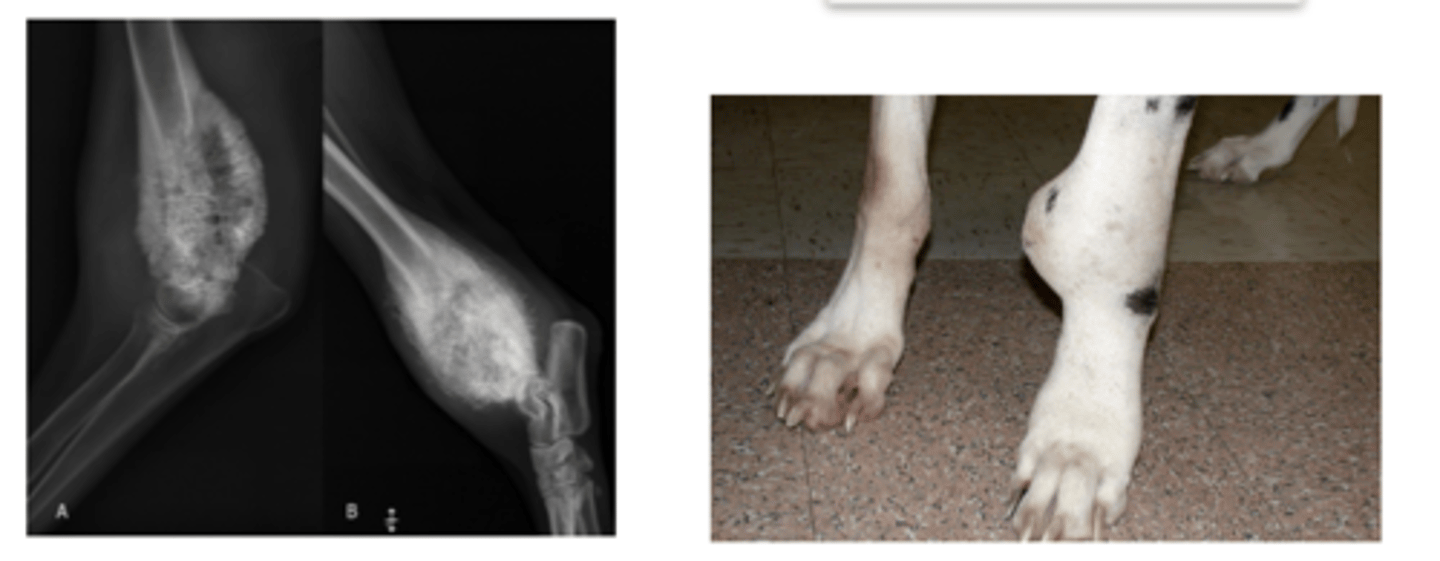

osteosarcoma

what is this called?

panosteitis

what is the problem here?